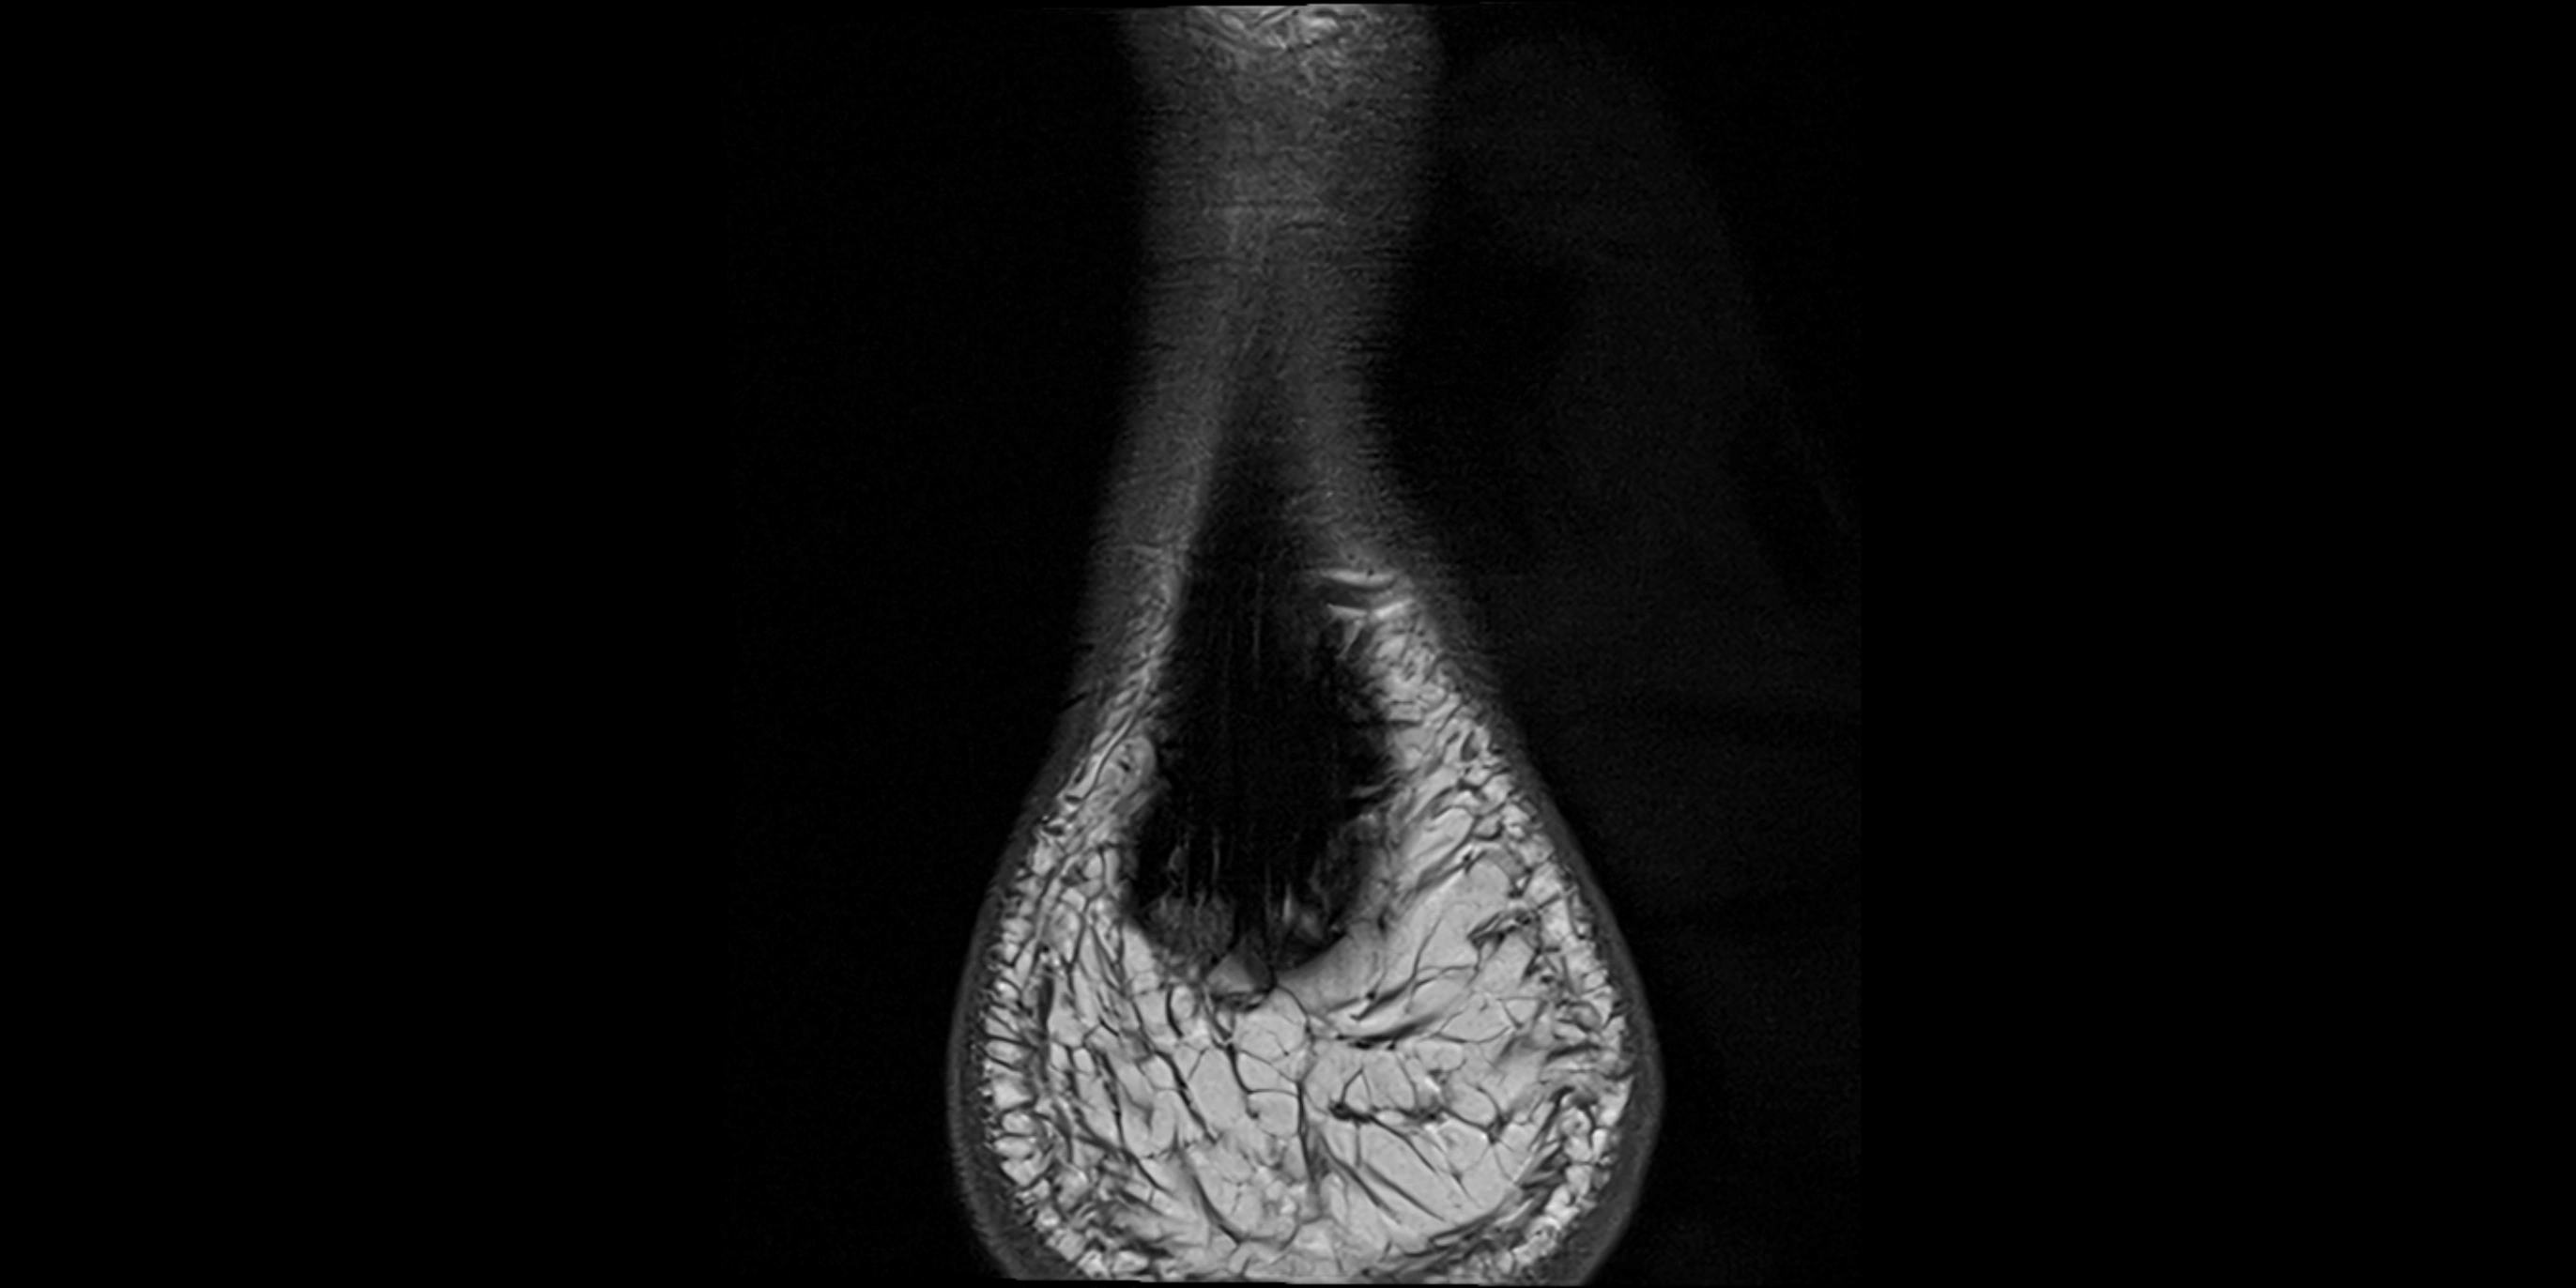

MRI image

image